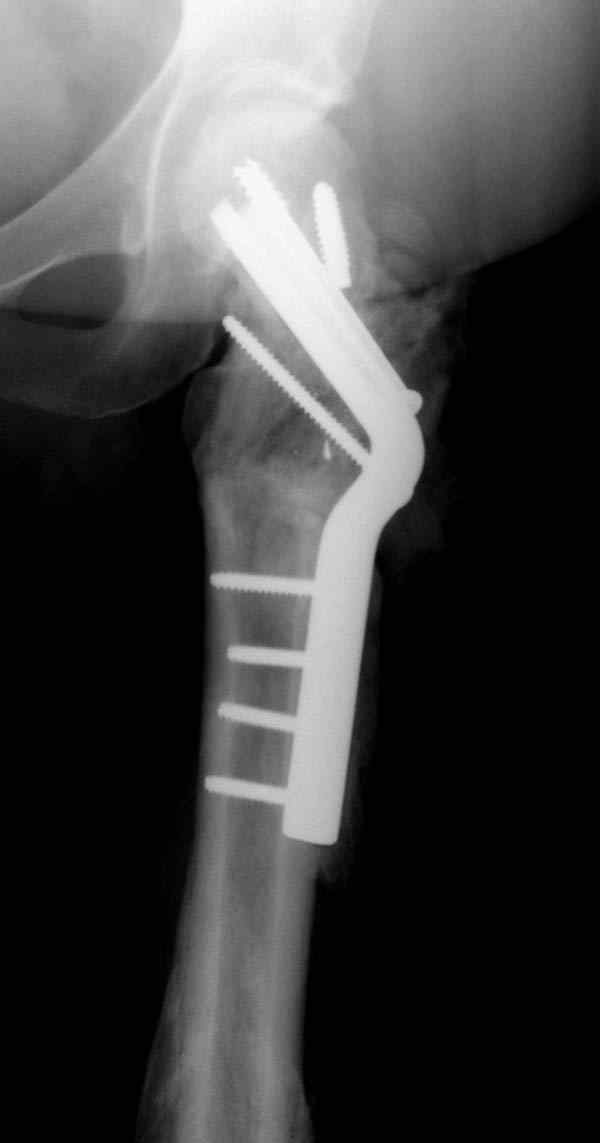

Имя     : missed neck.JPG

Тип     : image/jpeg

Размер  : 10415 байтов

Url     : http://weborto.net:8080/pipermail/ortho/attachments/20080114/94c631b9/attachment-0008.jpeg